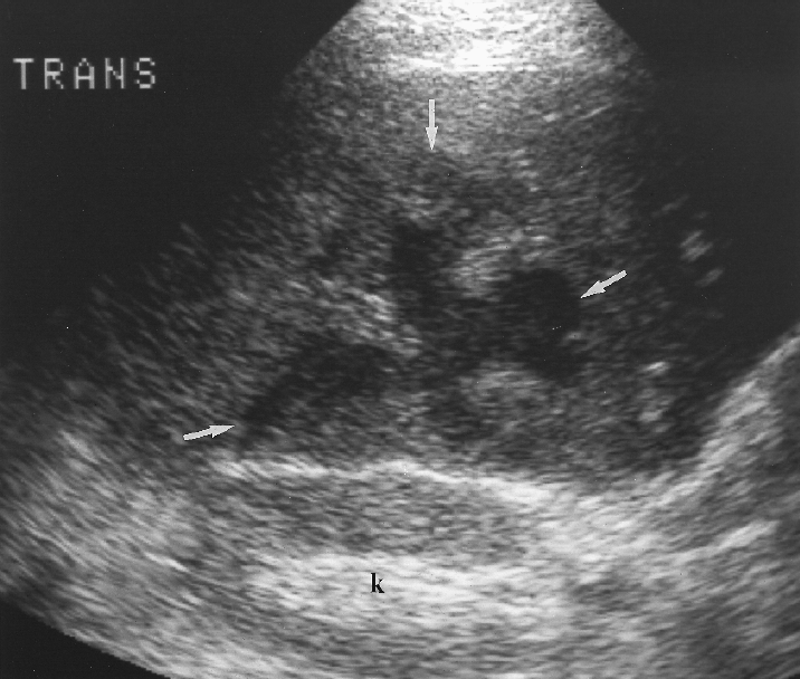

What is Polycystic liver disease?

This is an autosomal dominant genetic disease in which multiple small cysts cover the liver. 60% of patients with polycystic liver disease will have polycystic kidney disease.

What is the sonographic appearance of Polycystic liver disease?

Anechoic

Thin well-defined walls

Posterior

enhancement

Multiple

Varying in small size